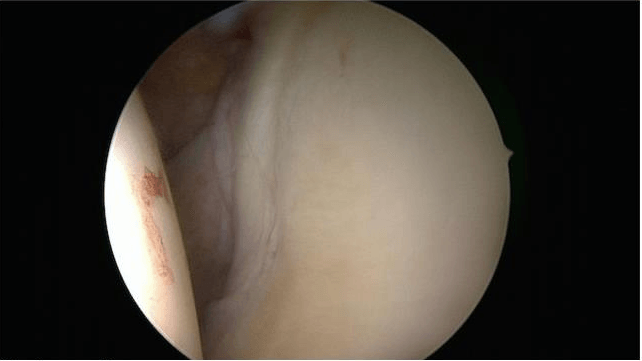

El rodete glenoideo es un fibrocatílago que contribuye a la estabilidad pasiva de al articulación gleno-humeral, junto con la cápsula y la superficie articular. Sobre la parte superior del mismo se inserta el tendón de la porción larga del bíceps, que se hace intraarticular.

Conviene realizar un artro-escáner para localizar la lesión, aun así, solamente se detectan el 45% de los casos. Solamente la artroscopia exploratoria permite realmente realizar un examen de la articulación.